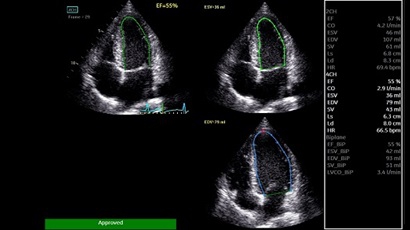

AUTO 2D EF:

Да

• AUTO 2D EF - режим автоматической недопплеровской количественной оценки глобальной сократительной функции ЛЖ (по Simpson).

• AFI - режим цифровой недопплеровской качественной и количественной оценки региональной сократительной функции ЛЖ.

• LVO CONTRAST - опция контрастирования полости левого желудочка.